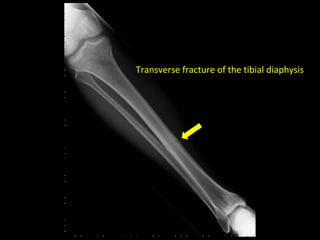

Transverse fracture of the tibial diaphysis

• 13.

How to describefractures • Describe the fracture line • Transverse, oblique, spiral – the majority of fractures can be described with one of these terms • Occasionally, fractures will be multidirectional, for example ‘t- shaped’, ‘h-shaped’

• 14.

Transverse fracture ofthe tibial diaphysis